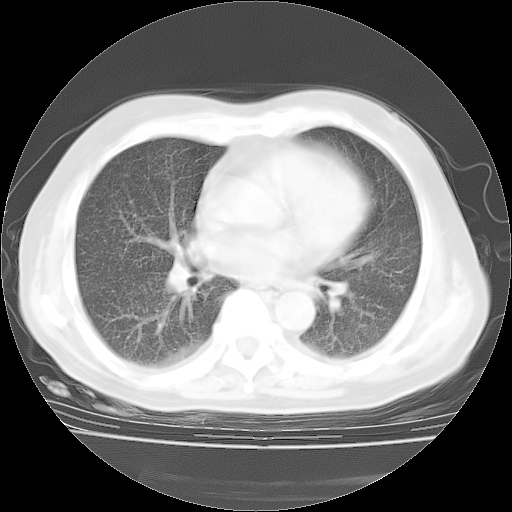

4月28日肺部CT——再次出现类似去年5月9日——磨玻璃样、间有“粟粒样”改变。